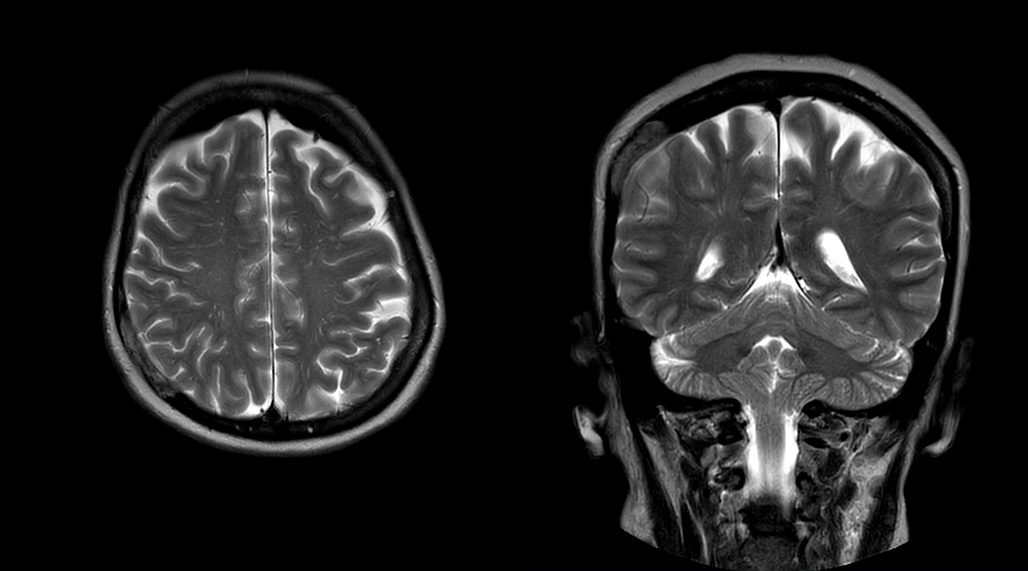

“Obviously, the diagnostic capability is most important,” says Dr. Kaakaji. “Ingenia’s image quality is excellent and in follow-up studies, Ingenia provides good consistency between scans.

“Without using an endorectal coil we do our prostate MR at 0.5 mm resolution, following the European society of urology protocol [1]. For certain joints we use a virtual arthroscopy protocol with 1 mm pixel size and 2 mm slice thickness. Ingenia really excels in our neurography, brachial plexus and prostate scans. Our neurologists insist on using our 3.0T for those,” Dr. Kaakaji adds.

DMG recognizes MultiVane XD motion compensation is another Philips technique that contributes to image quality and scan efficiency. “We run MultiVane XD for motion-free imaging on almost all our T2-weighted brain scans, just to reduce any repeats we might get. We know our non-contrast brain scans are going to take 20 minutes almost every time,” Mr. Duffy says.

“Using MultiVane XD still allows us to turn on dS SENSE, which significantly cuts scan time compared to what we were doing before,” he adds. “We went from a 2.5 or 3-minute scan to a 1.5-minute scan with no loss in image quality. So, it not only reduces the motion, but also reduces scan time. That gives us a little bit of extra time to speak to our patients and explain the exam a little more.”